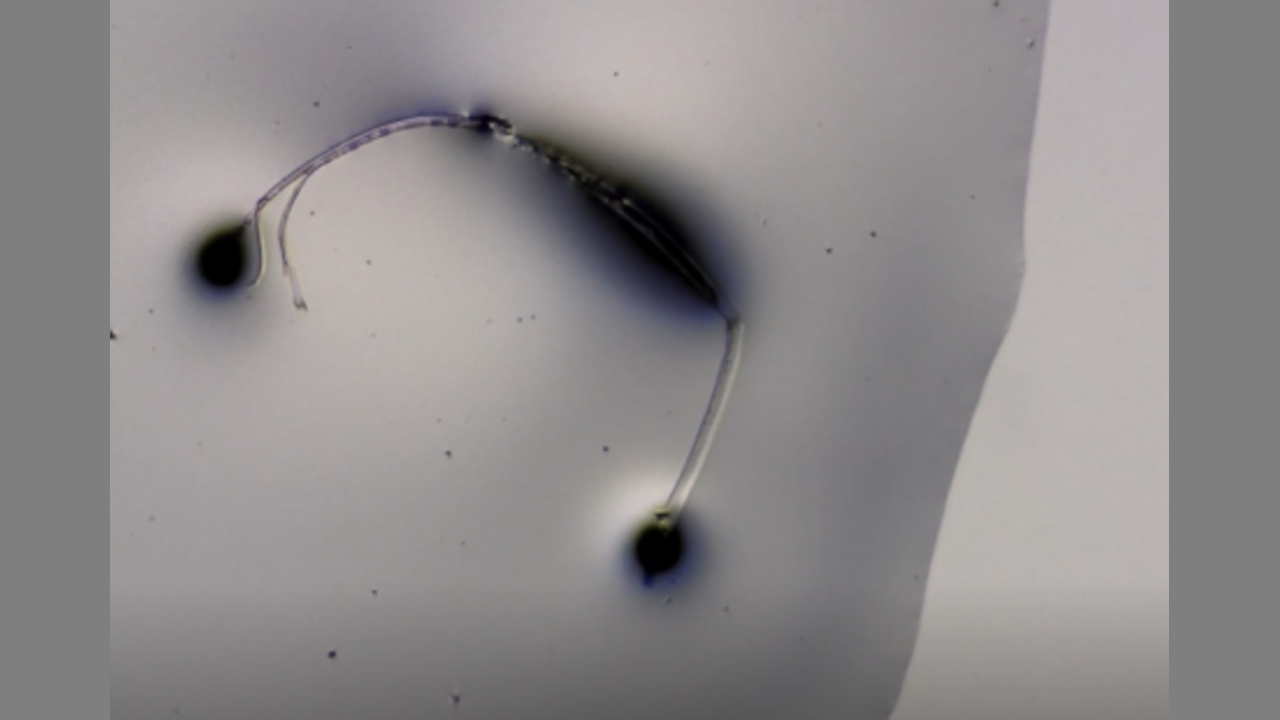

Anestesia Local bajo el micoscopio -- Local anesthesia under the mycoscope